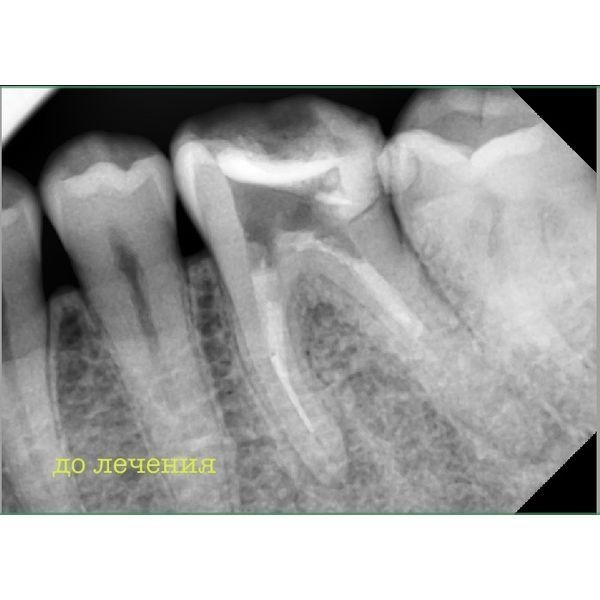

Прицельная рентгенография показала:

- слабоконтрастный пломбировочный материал неоднородной структуры в каналах;

- фрагмент инструмента в нижней трети язычного корня зуба;

- очаги снижения минеральной плотности костной ткани в верхушках переднего и заднего корней зуба.